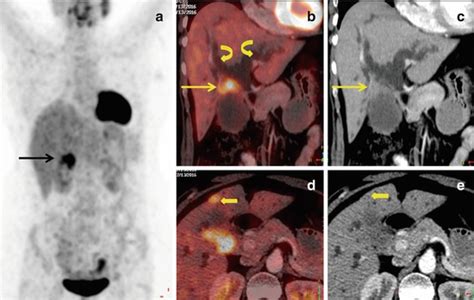

Recognizing the symptoms and seeking timely diagnosis are absolutely critical when it comes to ICD-10 Code C24 related cancers. As we’ve mentioned, jaundice is a hallmark symptom, often accompanied by intense itching. Patients might also experience dull or aching pain in the upper right abdomen, which can sometimes radiate to the back. Unexplained weight loss, loss of appetite, fatigue, and changes in the color of urine (darkening) and stools (becoming pale or clay-colored) are also significant warning signs. Because these symptoms can be vague and mimic other less serious conditions, diagnosing biliary tract cancer often requires a multi-faceted approach. Doctors will typically start with a thorough medical history and physical examination. Blood tests are essential to check liver function, bilirubin levels, and tumor markers. Imaging studies are crucial for visualizing the biliary tree and detecting any abnormalities. These may include ultrasound, CT scans, MRI scans, and MRCP (Magnetic Resonance Cholangiopancreatography), which provides detailed images of the bile ducts. In some cases, an endoscopic retrograde cholangiopancreatography (ERCP) might be performed, which allows doctors to both visualize and potentially biopsy suspicious areas. A biopsy is often the definitive diagnostic step, where a small tissue sample is taken and examined under a microscope to confirm the presence and type of cancer. The diagnostic process can be lengthy and stressful for patients, highlighting the need for compassionate care and clear communication from the medical team throughout the evaluation.